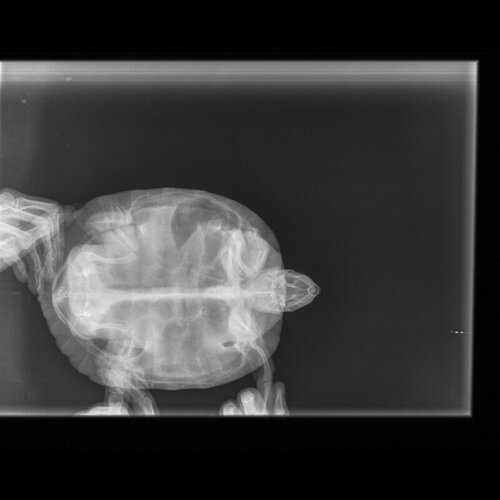

Добрый день.Вчера делали рентген красноухой черепахе,ей ставили диагноз пневмония 14 мая, кололи антибиотик Байтрил  12 дней и Дексометазон 7 дней, глюкозу 4 дня,так как ничего не ест. Если кто-то может и понимает в рентгене, прошу проконсультировать.

по такой проекции невозможно увидеть лёгкие черепахи и подтвердить или опровергнуть пневмонию